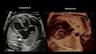

Normal Fetal Cardiac Anatomy: The Great Vessels & Upper Mediastinum

Alfred Abuhamad, M.D.